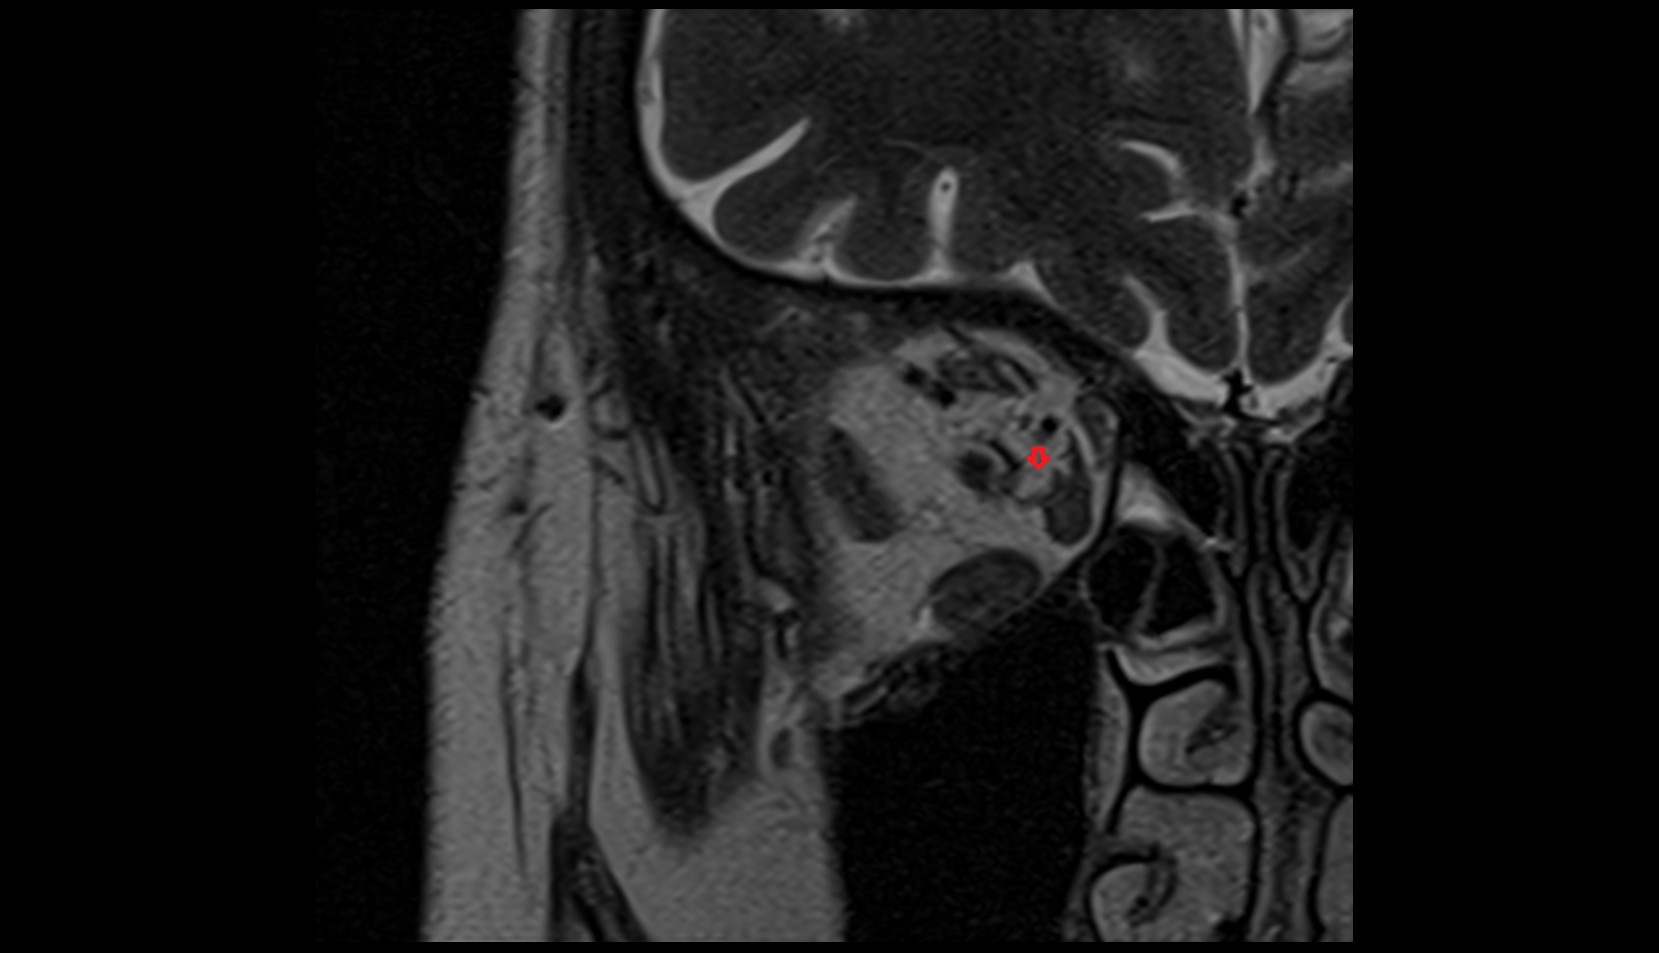

- Uterus

- Body of uterus

- Fundus of uterus

- Cervix of uterus

- Isthmus of uterus

- Vagina

- Fornix of the vagina

- Endometrium of uterus

- Myometrium of uterus

- Perimetrium of uterus

- Junctional zone of uterus